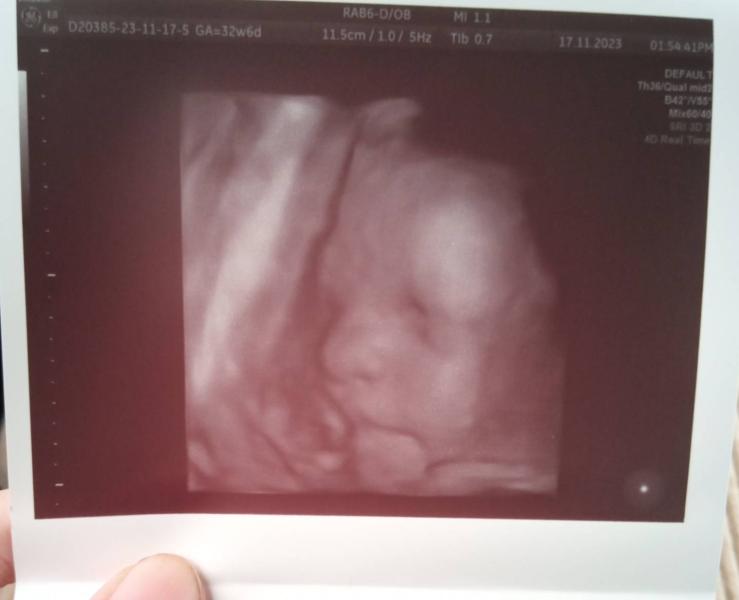

Срок 32 недели

У нас все хорошо соответствует своему сроку, врач узист сказала что будет волосатой, лежим головкой вниз и это очень замечательно, пиэлоктазия сохранилась на втором скрининге правая лоханка была 4.2 сейчас 6.2.

Вес малышки уже 1800

Моя маленькая щекастая принцесса жду не дождусь нашей с тобой встречи